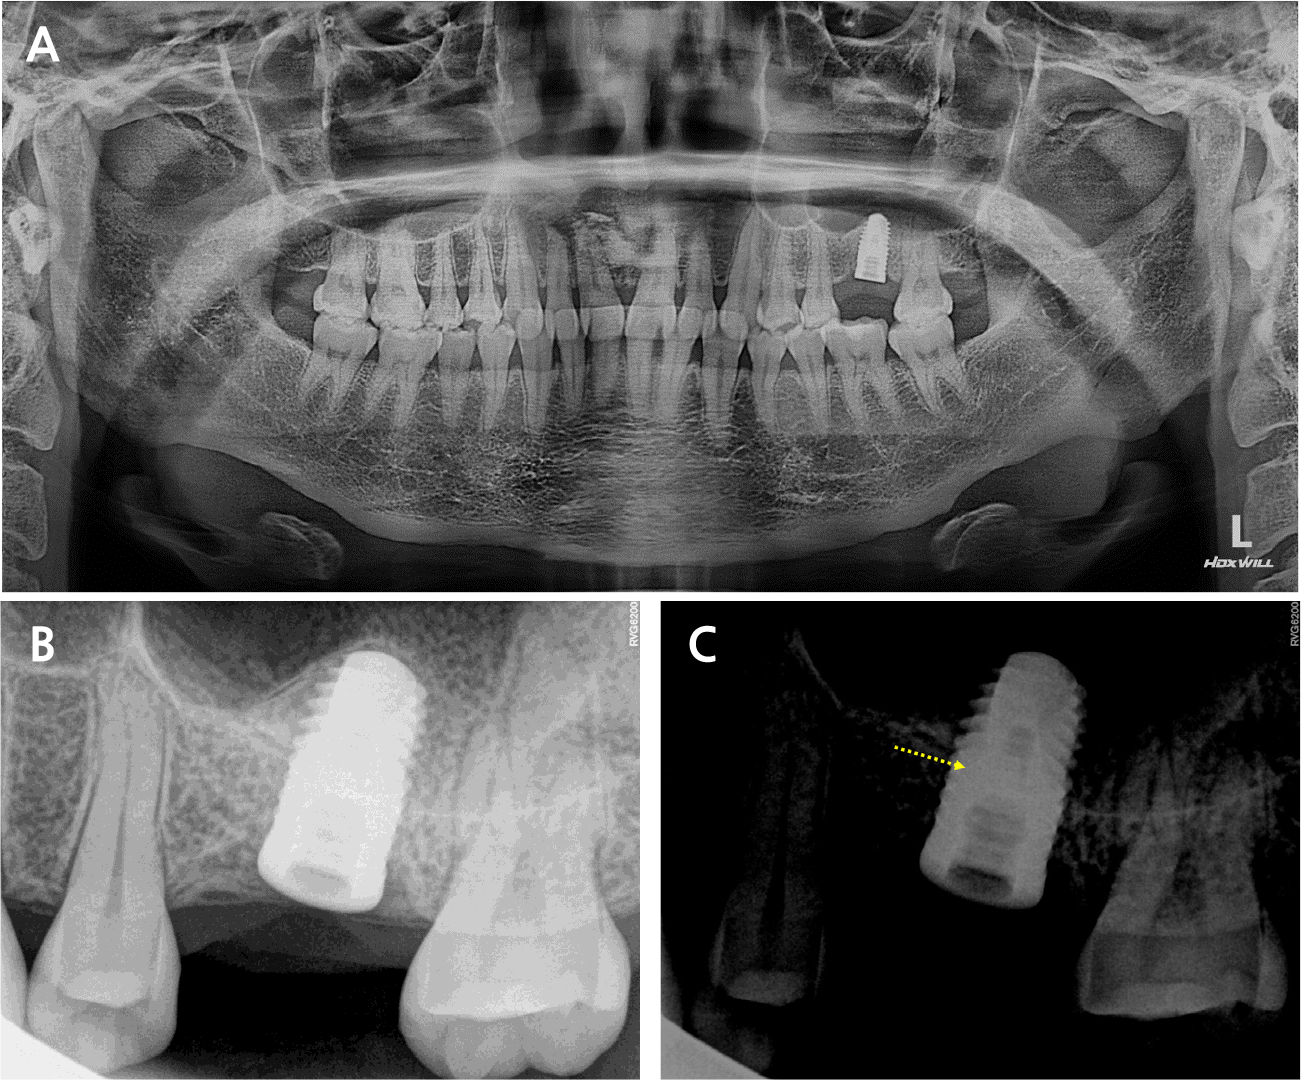

A 42-year-old female patient visited our dental clinic because of mobility of an implant prosthesis at the left maxillary first molar. According to the dental history, the implant (Xive® 5.5 × 11 mm; Dentsply Sirona, Charlotte, NC, USA) had been placed 10 years before at another dental clinic. A screw-retained porcelain-fused gold (PFG) prosthesis was connected to the patient. After retrieving the implant prosthesis, an abutment screw fracture was observed (Fig. 1).

The radiograph revealed < 1 mm of marginal bone loss around the implant without inflammatory signs or peri-implantitis. The fractured screw left inside the implant was observed in the panoramic and periapical views (Fig. 2) and was located 7 mm deep from the soft tissue. An explorer, an ultrasonic scaler, and a removal kit (Neo SR Kit-II; Neobiotech, Seoul, Korea) were used for screw removal. However, the removal was difficult because the fracture was located at the first screw thread, and the remaining screw had been preloaded with torque. Sequentially, a high-speed handpiece with a 1/2 round bur was used to carefully remove the screw fragments remaining inside the implant fixture. The screw fragments inside the fixture were successfully removed, but the internal thread was damaged, and the healing abutment was not completely connected.